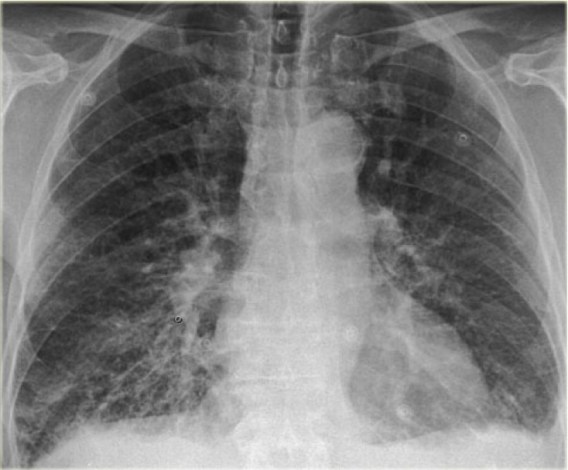

CASO: Operada de esofaguectomia y reconstrucción con coloplastia hace 3 meses. Sintomas de neumonía.

Hallazgos:

- De inicio llama la atención una densidad practicamente total del todo el hemitórax izquierdo, lo cual podría hacernos pensar que estamos ante una posible neumonía.

- Sin embargo el tórax está no está bien centrado, observar como la clavícula izquierda se encuentra casi en la mitad del pulmón, por tanto lo que vemos blanco es el mediastino ya que el tórax está rotado.

Mismo paciente, al cual esta vez se le ha tomado una radiografía en PA y en sedestación. Observar como las clavículas están equidistantes a las apófisis espinosas y como ha desaparecido el velamiento del pulmón izquierdo.

Por otra parte, paciente presenta una cardiomegalia y un discreto ensanchamiento del mediastino es probable relación con cambios postquirúrgicos.